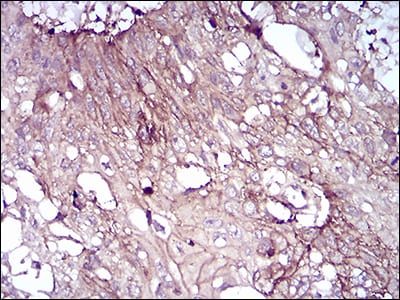

分类: 科研抗体货号: 30742别名: SSH1;SSH1L应用: IHC,FCM反应种属: Human